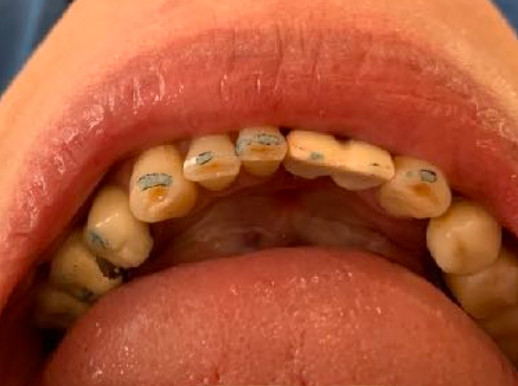

Non esistono bocche perfette, non ci sono organismi perfetti. Come medici/odontoiatri possiamo solo augurarci di incontrare bocche normali, anche se molto spesso non è così. E con il passare degli anni è più facile perdere salute e normalità piuttosto che trovarle. Consumiamo lo smalto, si abbassano le gengive, si approfondano le tasche, si cariano le corone.

A volte le consumiamo noi stessi col serramento, col bruxismo o perché le spazzoliamo con troppa energia. Perdiamo in seguito i denti per varie cause e così si abbassa il livello dell’osso. E alla fine perdiamo la vita stessa. Quante volte siamo stati o ci siamo sentiti perfetti? E allora.... Sorrido con amarezza ogni volta che sento colleghi cattedratici declamare il ritorno alla perfezione estetica e funzionale del sorriso dei loro pazienti. Noi no! Noi non crediamo a questa dichiarazioni false e ingannevoli. E non crediamo neppure che a questo siamo tenuti legalmente.

Noi crediamo che sia indispensabile riportare ad una funzionalità normale la bocca dei nostri pazienti. E l’estetica solo per quanto è possibile: appunto al meglio. Anche i nostri pazienti lo sanno. Nonostante l’apparire giovani sani e belli sia il target della nostra società. In primis la funzione! Abbandonato l’inutile e falso obiettivo della perfezione estetica possiamo cominciare ad avere rispetto della integrità e delle buone qualità residue dell’apparato masticatorio del nostro paziente. Usando e rispettando il suo osso dove è presente. Senza devastarlo con inutili scollamenti, dissezioni per regolarizzare la cresta, atrofie indotte da lunghe attese di guarigione. Ad esse seguono perforazioni inutilmente estese con ulteriori perdite di osso, coronate poi da impianti che debbo riconoscere sono molto ben reclamizzati ed in costante evoluzione. A meno che poi il collega sospirando dichiari che l’osso manca e che bisogna fare un innesto. E la via crucis ricomincia... Mi scuso per lo sfogo. Gli impianti che uso sono praticamente identici al modello creato nel 1963 dal dott. Tramonte Stefano. E i miei pazienti si trovano così bene che io considero l’impianto di TRAMONTE pari almeno ai migliori prodotti del mercato, senza averne i difetti. Mi spiegherò meglio più avanti. Nelle prossime news.